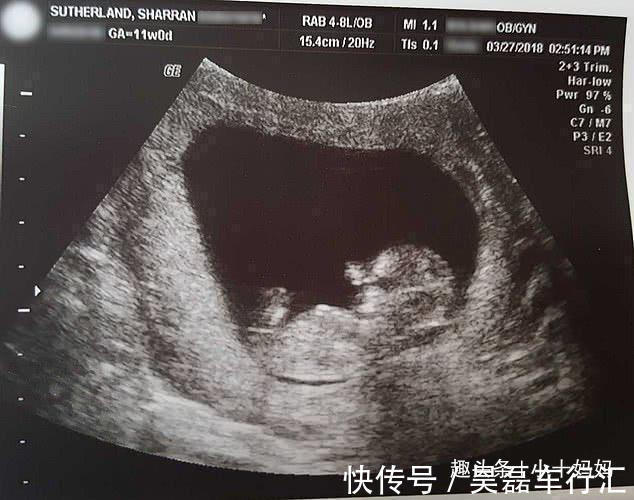

婴孩|女子流产后,将14周“孩子”放进冰箱并分享,照片中孩子仅10厘米

这位来自外国的女人本应该做一个快乐无比的妈妈,可是在怀孕14周的时候,医生的一句话让他顿时间抛弃了这样的想法。医生表示:很抱歉,你的孩子流产了。当听到这句话之后这位女人就像是疯了一样,他根本不相信医生说的话是真的。但是事实就摆在眼前,不相信也是没有办法的。因此医生希望他做刮宫手术,可是这位女子却拒绝了,因为她实在是不想看到自己的孩子被切成碎片。于是女子选择自然分娩,因为她从来都不觉得自己的孩子是医疗垃圾,所以女子还为宝宝取了一个名字叫米兰。

要知道14周的婴儿仅仅有了人的形状而已,但与正常的婴儿还是有着一定的差距的。不过这位女子并没有放弃死去的婴孩,而是选择把婴孩儿冷冻,为了防止婴儿腐烂,女子还特意将婴孩摄入了生理盐水,最后把婴孩儿放在了花盆里。女子每一年都能看到花盆在开花,女子曾表示能见到这一幕,也算是自己的幸运了。